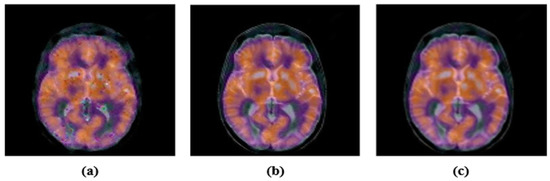

2.3. Accurate Computation of New Multi-Channel Gaussian-Hermite Moments of Color Images

3. Proposed Zero-Watermarking Algorithm